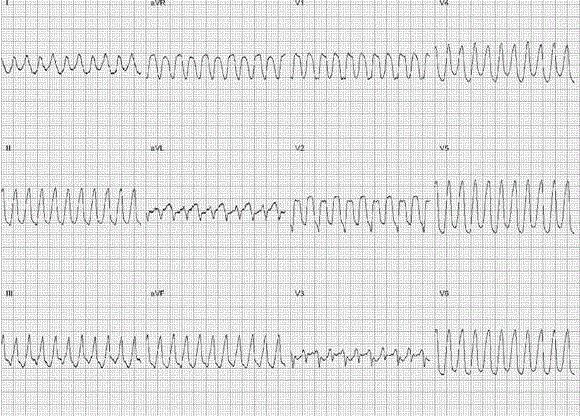

问题  患者男,57岁,因反复活动后气促1年余,加重伴咳嗽2周入院。无高血压、高血脂、糖尿病等病史。 心电图诊断为(提示 住院过程中,于排粪后突然倒地、抽搐,立即行心电图检查,如下。)

选项 A、预激综合征合并心房颤动 B、右心室单形性室性心动过速 C、心室扑动 D、左心室单形性室性心动过速 E、尖端扭转型室性心动过速 F、双向性室性心动过速 G、室上性心动过速伴左束支传导阻滞 H、心室颤动

答案 B